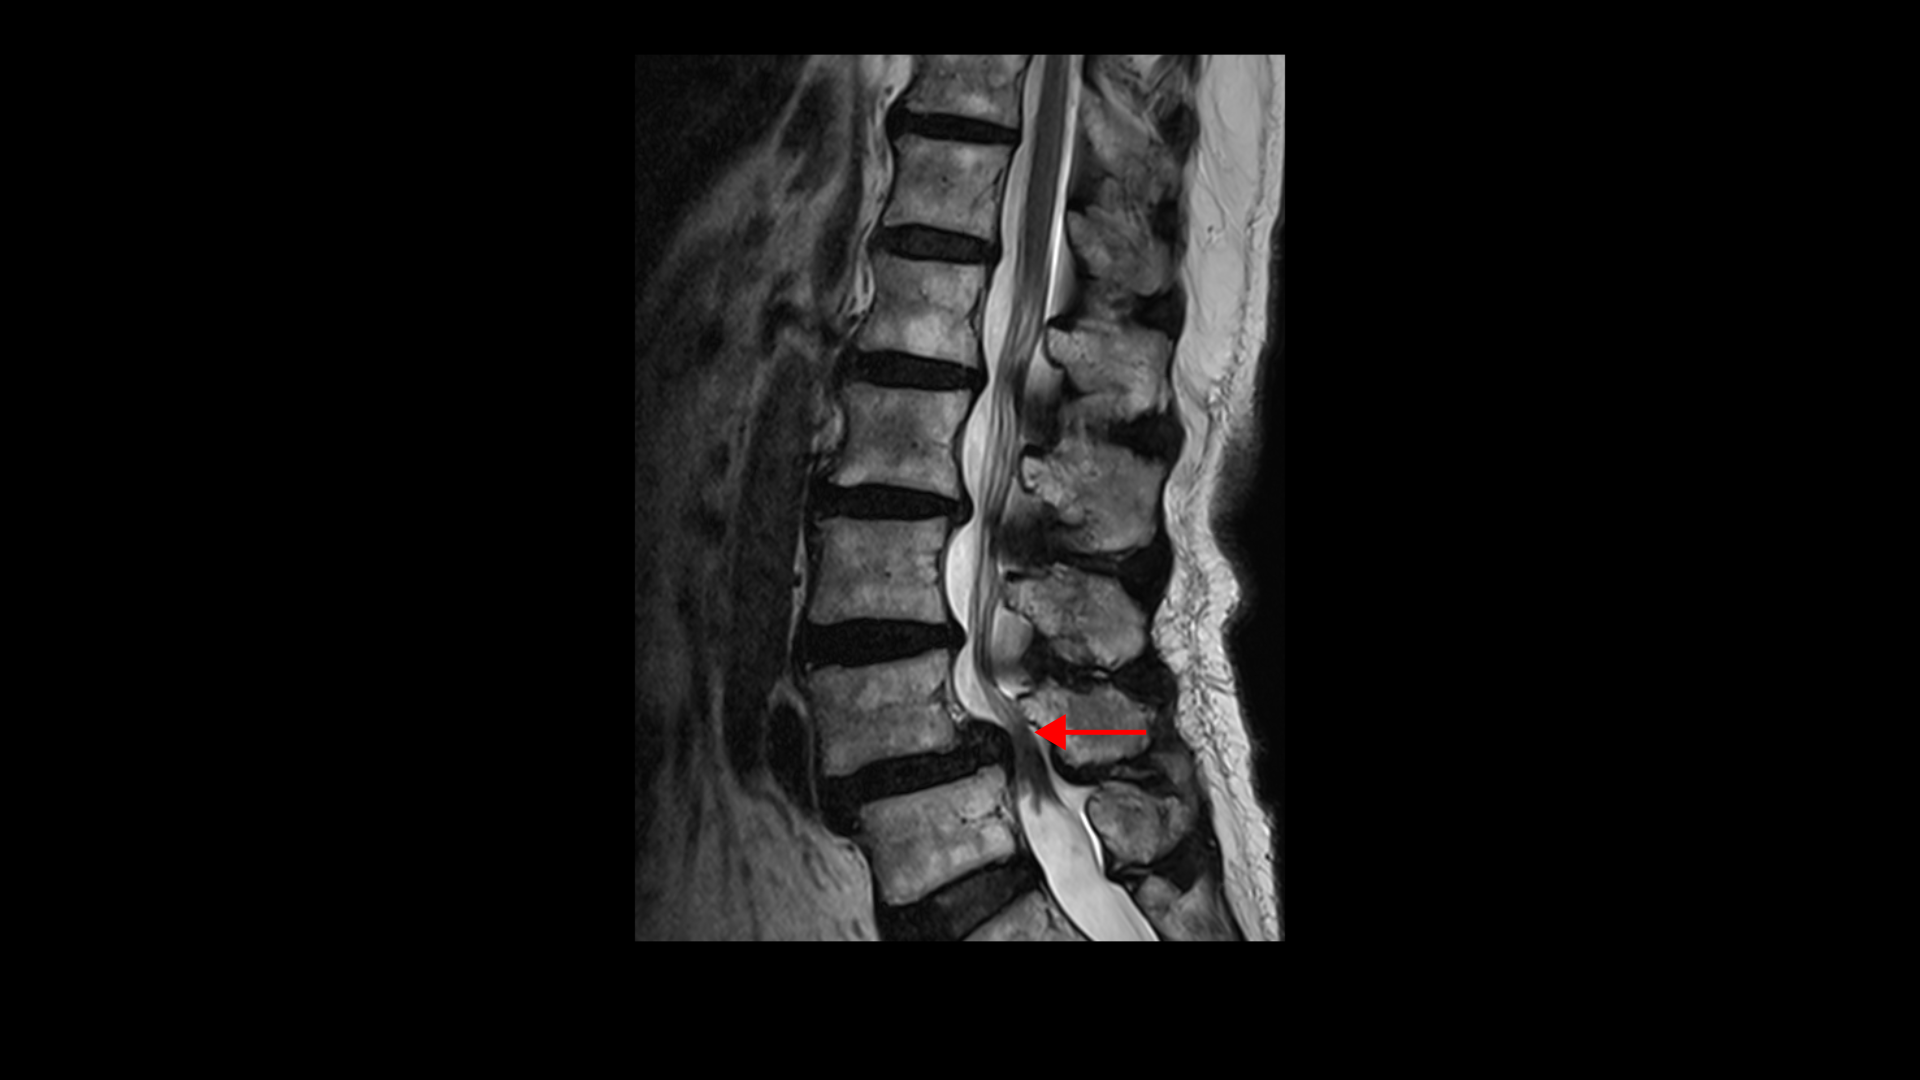

이 환자분 상태를 먼저 설명 드린 후 이분 말씀을 들어보겠습니다. 이분은 협착증을 앓으신 지 약 7년 정도 되셨습니다. MRI를 보면 여러 마디에 퇴행성 디스크가 있고

4번, 5번에는 전방전위증이 있습니다.

전방전위증이 있는 4번, 5번 마디에서는 오른쪽, 왼쪽 신경가지가 나가는 양쪽 추간공이 모두 좁아져 있고

그리고 척추관도 황색인대가 심하게 두꺼워지면서 중심성 협착도 매우 심합니다.